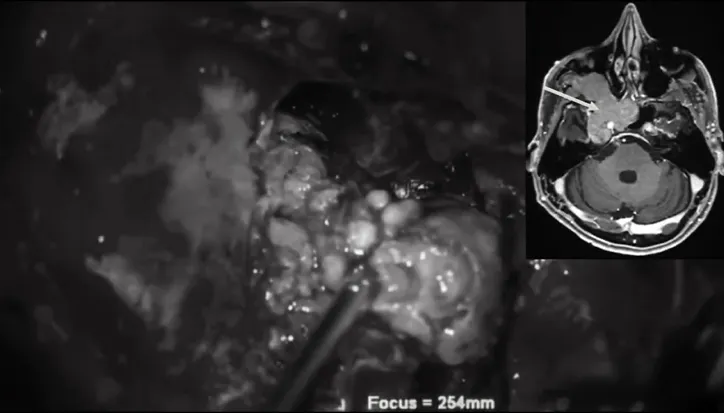

显微镜外科手术分步取出肿瘤图解

▼后颅窝部位肿瘤顺利切除

▼翼腭窝部位肿瘤顺利切除

▼翼腭窝到颞下窝部位肿瘤顺利切除

▼前内侧三角部位肿瘤切除

▼蝶窦部位肿瘤切除